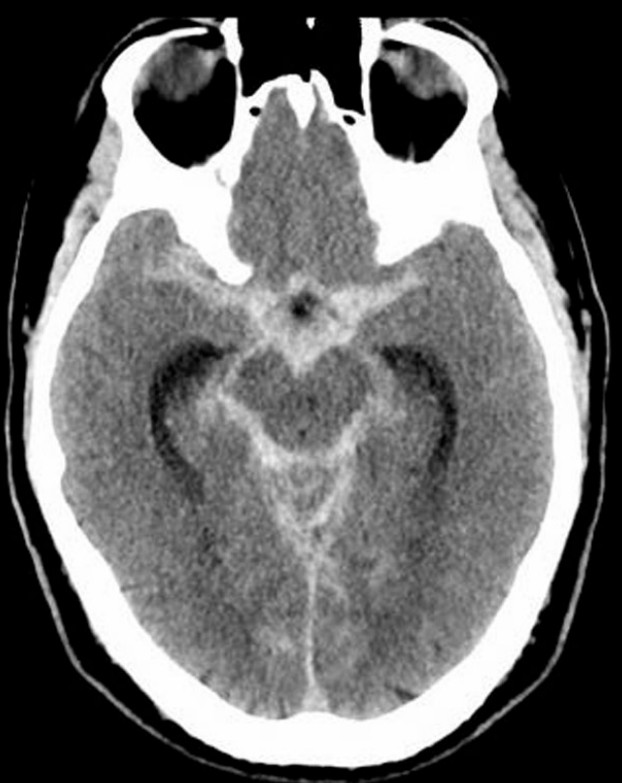

Sudden severe headache

A 34-year-old woman has presented with a sudden onset, severe headache and vomiting. GCS 14 HR 100 BP 190/110 RR …

Subarachnoid haemorrhage

A 43-year-old woman arrives via ambulance to your regional ED at 8pm. She had a sudden worsening of a 2-day …